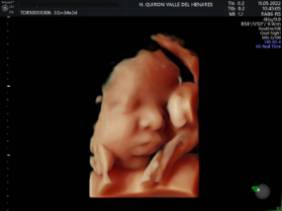

El Hospital Quirónsalud Valle del Henares incorpora un nuevo ecógrafo con tecnología 5 D

El Hospital Quirónsalud Valle del Henares ofrece la posibilidad de realizar ecografías gestacionales 5D. Este tipo de exploración permite obtener una imagen muy realista del bebé y se puede realizar en cualquier etapa de la gestación -aunque lo recomendado es realizarla entre las semanas 28 y 32 de gestación, ya que técnicamente es el mejor momento y es mucho más probable obtener imágenes de buena calidad-.

Al final de la prueba, se entrega a la familia un informe de la ecografía y un soporte digital que contiene las imágenes y los vídeos realizados. Las ecografías 4D y 5D son también llamadas emocionales por la explosión de sensaciones que genera cuando la madre ve por primera vez la imagen del bebé que espera.

"Realizar esta ecografía con nuestro equipo de diagnóstico prenatal tiene un valor añadido -señala la Dra. Rocío Vellido Cotelo, Jefa Asociada de Ginecología y Obstetricia del Hospital Quirónsalud Valle del Henares, dado que quien realiza la prueba es un especialista en la materia, siempre se completa la exploración con un examen morfológico y de perfil biofísico fetal, que permita valorar el estado de bienestar del bebé más allá de la captura de videos y fotografías".